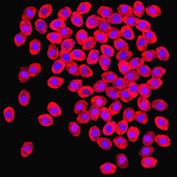

appropriate simulation algorithm. Figure 2 shows some examples of the obtained

Figure 2. Simulated synthetic images

images.similarity of experimental and generated synthetic images is not enough

real experimental images. That is why numerical comparison of the available

experimental images of cancer tumors and reproduced synthetic images was drawn.

The analysis of the intensity histograms of the affected

cells nuclei on simulated and experimental images in three colour channels was

conducted. The results showed similarity of the images intensity. The χ2 goodness of fit was used

to verify the quality of modelling and showed that the values did not exceed

critical values of χ2 at a significance level of 0.95

indicating that the statistical conditions of χ2 were satisfied., the

equivalent radii of nuclei on the experimental image were compared with those

on the simulated synthetic image. The χ2 goodness of fit was used

again for the objects distribution histogram according to the value of their

equivalent radii to check their conformity with the laws of distribution. The

calculation of χ2 values for 19 degrees of freedom

gave 9.61 which was less than the critical value of χ2 equal to 10.1 at a

significance level of 0.95.the process of cancer tumor cells modelling several